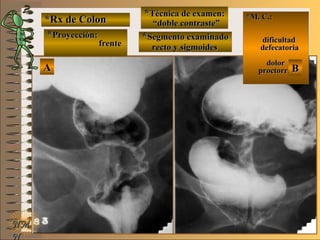

*Rx de Estómago*Rx de Estómago

**Proyección:Proyección:

**Técnica de examen:Técnica de examen:

A-A-

B-B-

C-C-